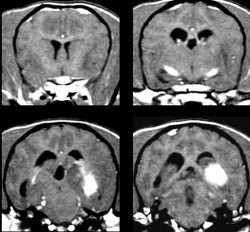

●肉芽腫性髄膜脳脊髄炎 (GME)

上記の脳炎はいわば、「脳細胞が壊される」疾患ですが、こちらは肉芽腫といわれる、塊状の炎症が脳にできるものです。脳神経に「腫れ物」ができるイメージです。

したがって、脳腫瘍に類似しているとも言えます。脳を圧迫することも多い為、様々な症状を呈してきます。

脳内の色々な場所に生じ得ます。このGMEには、「眼型」というタイプがあり、突然の視力消失など眼の症状で発見されるものがあります。これは、GMEの初期病変なのか